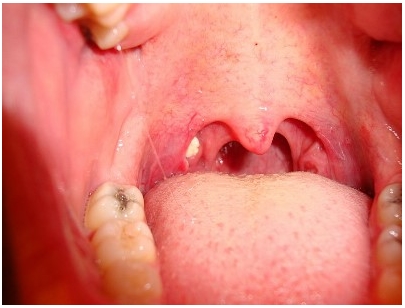

- 편도결석, 후두염, 부비강염, 기관지확장증 등의 호흡기질환 – 충치, 치아플라크, 치주염, 구강건조증 – 심리적 불안 – 위식도역류, 간질환, 신장질환

그러나 대부분은 편도결석에 의한 입냄새로 스트레스를 받고 있습니다.